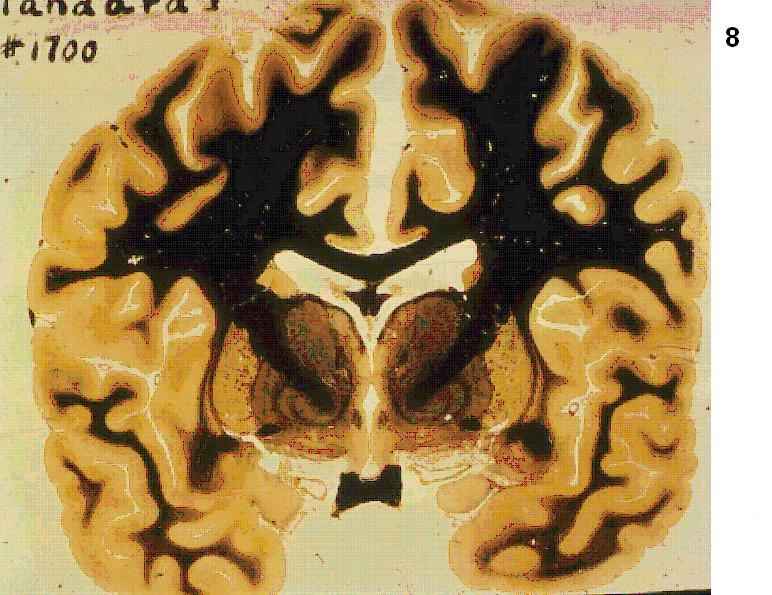

Figure 4 Figure 5 Figure 6 Figure 7 Figure 8 Figure 9 Figure 10 Figure 11